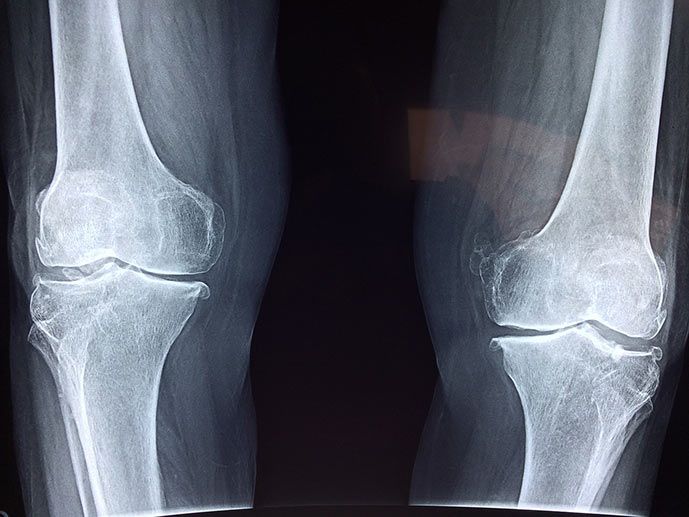

Rarefazione del tessuto osseo conosciuta come Osteoporosi

L’osteoporosi è una rarefazione del tessuto osseo che comporta una minore resistenza dell’osso e un maggior rischio di frattura.

Dal punto di vista fisiopatologico comporta una diminuzione della densità e della qualità ossea.

La principale è data dalle fratture i siti principali sono: la colonna vertebrale, l’anca, l’avambraccio e l’omero prossimale.